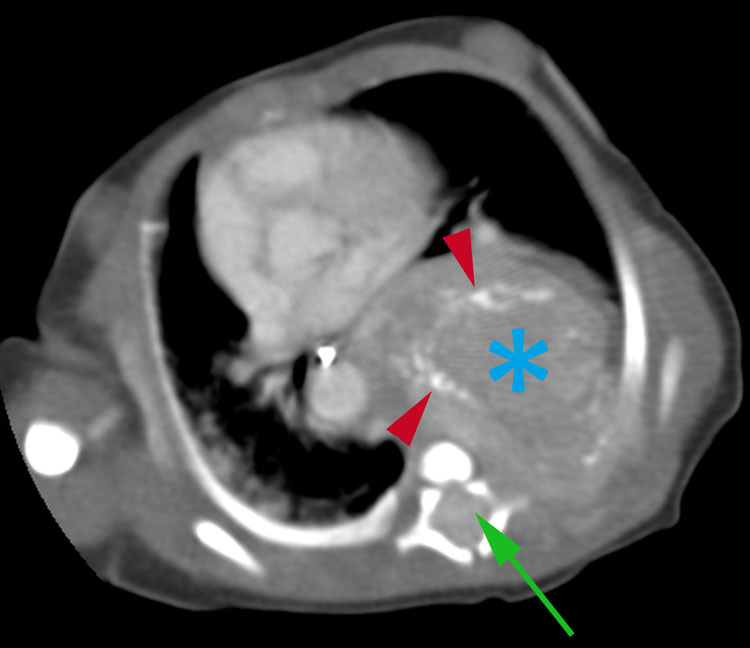

Diagnosis?

Congenital pulmonary adenomatous malformation.

Presents as mass lesion containing several large cysts or multiple small cysts, rarely can appear solid.

Types of CPAM?

Type 1- large cyst(s) > 2 cm.

Type 2- numerous small cysts.

Type 3- appears solid.

What is a CPAM?

A hamartoma consisting of abnormal terminal bronchiolar proliferation with a relative paucity of alveoli.

Bronchial communication present congenitally.

Small risk for malignant transformation.